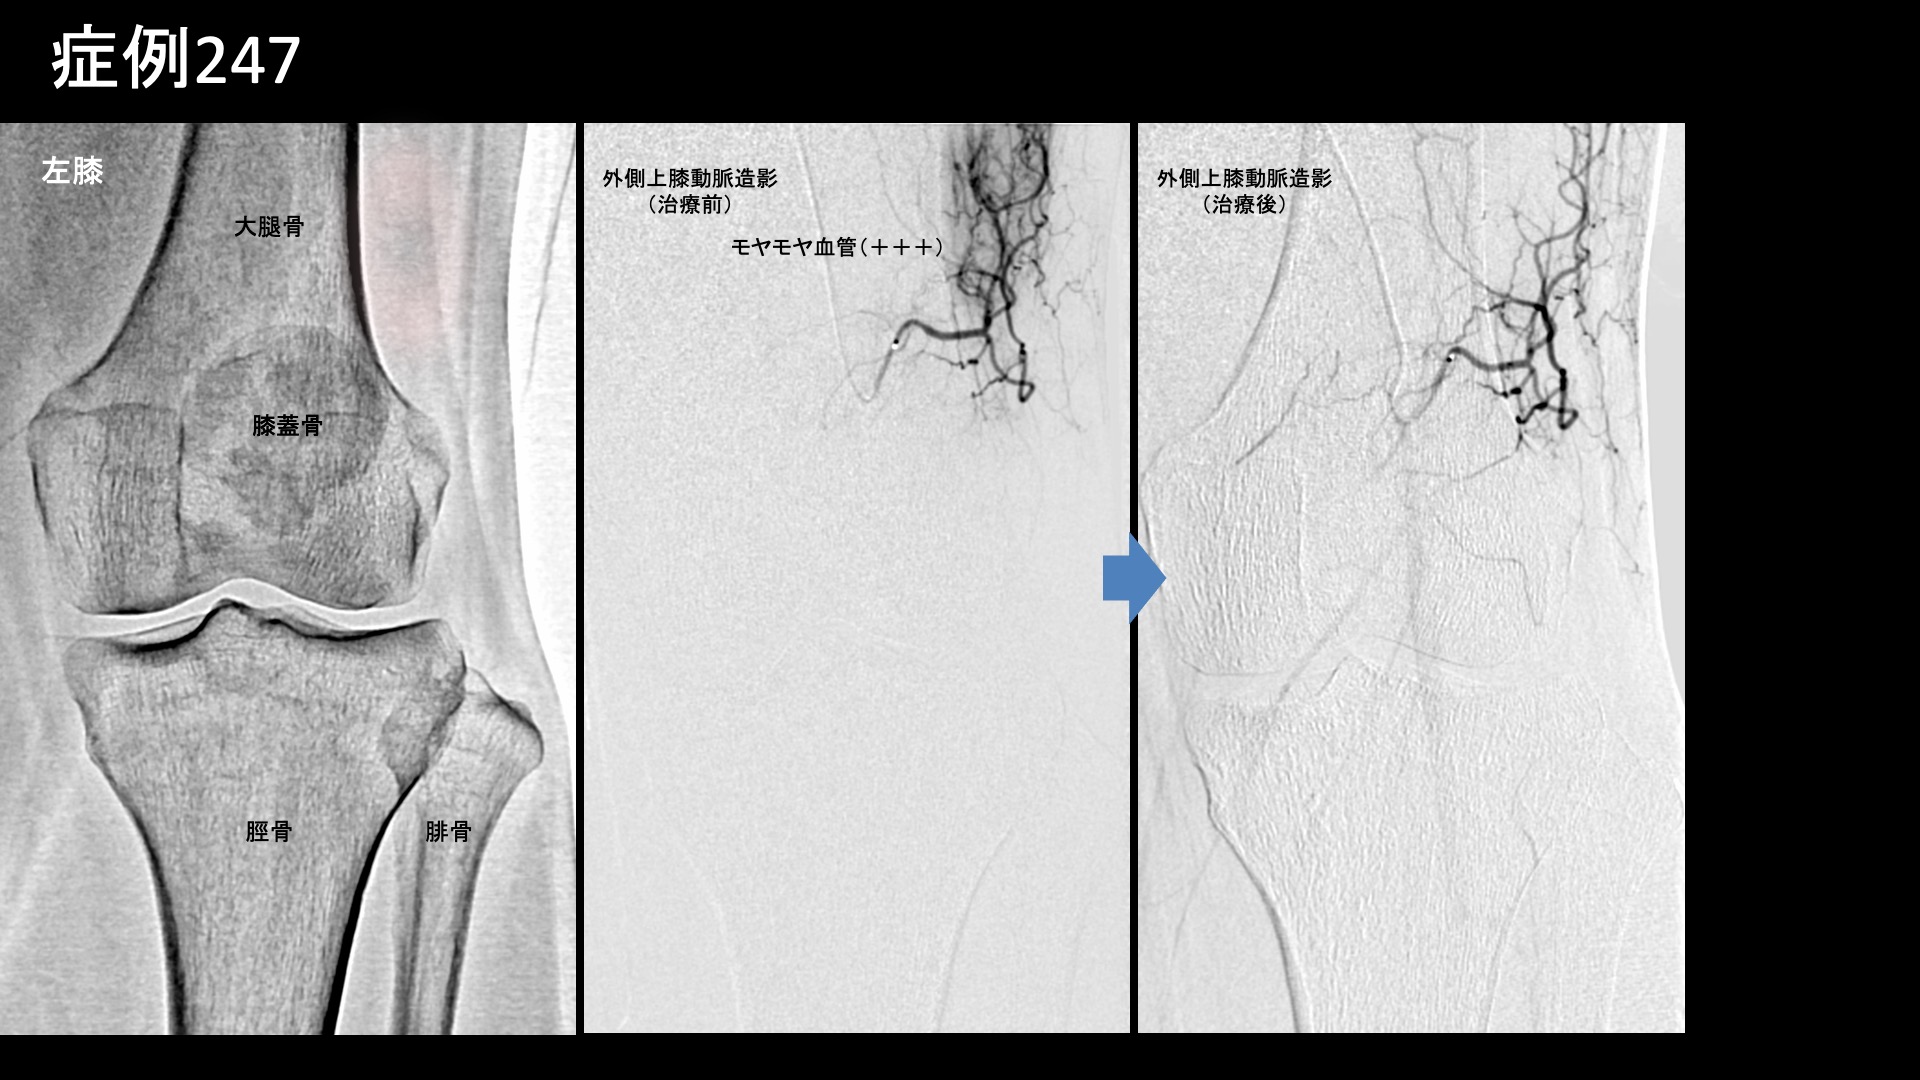

膝:変形性膝関節症など 【50代:女性】長い距離を歩くと痛くなる、登山家に生じた両膝の痛みに対するモヤモヤ血管治療(膝蓋下脂肪体炎、腸脛靭帯炎) 2025.11.05 鴨井院長による動画解説 受診までの経過 日常的に登山をされる方です。10年前に階段で転落してコンクリートの地面に両膝を打撲したことがありました。以前から、登山下山時に両膝が少し痛くなることがありましたが、1年半前頃に3-4時間程度の登山後に強い痛みがあったため、整形外科を受診しました。MRI検査の結果、軟骨の磨り減りはほとんど無く、膝蓋下脂肪体炎が疑われると言われました。2km以上歩くと痛くなり、その後2-3週間すると痛みが無くなります。3km以上になると、激痛になります。左右差は特にありませんでした。常に激痛があるわけではないものの、段々と歩ける距離が減ってきているため当院を受診されました。 診察時の所見 レントゲン、エコー検査とも変形性膝関節症の所見はありませんでした。膝蓋下脂肪体では、軽度の圧痛を認めました。MRIでも明らかな強い炎症ではありませんでしたが、両側膝蓋下脂肪体炎として矛盾せず、症状の性状からも治療による改善が期待されたため、モヤモヤ血管(病的新生血管)に対する運動器カテーテル治療(微細動脈塞栓術)を受けていただきました。 治療の所見 血管造影を行うと、両側の内側下膝動脈において、膝蓋下脂肪体に一致してモヤモヤ血管が濃染像として描出されました。更に左外側上膝動脈造影では、より豊富にモヤモヤ血管が濃染像として描出されました。術前の画像診断では明確ではありませんでしたが、症状の成因や、性状、この血管造影所見からは腸脛靭帯炎(代表的な、膝の外側の痛みの原因の一つ。別名ランナー膝。)の様相を呈していました。腸脛靭帯炎も合併していたのではないかと考えられます。治療後モヤモヤ血管は画像上速やかに消失しました。その他複数箇所の治療を行い終了しました。 治療前画像:損傷を受ける、あるいは繰り返しのストレスにより発生した異常な新生血管 治療後画像:カテーテルを用いて塞栓物質を血管内に投与し新生血管を塞いだ状態 治療費用:治療する部位によって費用が異なりますのでこちらをご参照ください。 主なリスク・副作用等:針を刺した場所が出血により腫れや痛みを生じたり、感染したりすることがあります(穿刺部合併症)。造影剤によるアレルギー(皮膚のかゆみ・赤み・息苦しくなるなどの症状)が出ることがあります。 治療後の経過 元々、少し長めに歩かなければ激痛は生じないため、治療後1ヶ月の直前に長めに歩いてみてもらいました。激痛は全く無く、階段を降りる際も、以前は他人の手を借りなければならなかったのが不要となっていました。まだ、熱い感じがしたり、それとは別に鈍い痛みを感じたりすることはありました。その後も順調に経過されたため、(良いことですが)受診はそれきりとなりました。追跡調査では、治療後3ヶ月時点で痛みは元の1/10程度、治療後6ヶ月ではほとんど痛みがゼロとなり、熱を持った感じも無くなりました。酷使して疲労が蓄積したときには鈍い痛みが出ることはありますが、それでも元の1/10程度とのことでした。膝蓋下脂肪体炎は比較的しつこい痛みの一つであり、完治するには少し時間がかかる傾向がありますが、ここまでくれば安心できます。無理のない範囲で登山を楽しんでいただければと思います。 膝蓋下脂肪体炎の詳細はこちら 【60代:女性】10年苦しんだ頭痛。考えがまとまらなくなり、家事もままならず。モヤモヤ血管治療により日常生活を取り戻すことができた実際の症例(筋緊張性頭痛、首肩こり、顎関節症) 前の記事 【60代:男性】痛くてドアノブも回せない、5年以上続いた手首の痛み。腱鞘炎に変形性手関節症を合併した一例(尺側手根伸筋腱の腱鞘炎、変形性手関節症、ドゥケルバン腱鞘炎) 次の記事